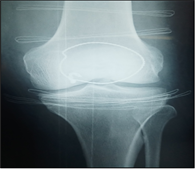

After a decline of six months (Figure 1), we identified one (01) case of pseudarthrosis or 5.88% and one (01) case of patellofemoral osteoarthritis or 5.88%.

(a) (b) (c) (d)

Figure 1. (a) Fracture of the patella, Duparc type II; (b and c) osteosynthesis by cerclage; (d) knee flexion at six months.